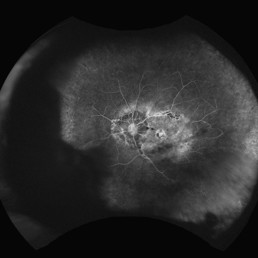

Fig 3. (R) A fluorescein angiogram showing the left eye of a patient with pathological myopia, posterior staphyloma and myopic maculopathy. The retinal vessels terminated at the edge of the posterior staphyloma with significant amount of peripheral non-perfusion but no neovascularisation

Pathological myopia associated with significant peripheral vascular changes

As Optos imaging becomes more widely available, these mostly benign peripheral retinal findings in patients with pathological myopia are being detected more frequently. In a paper published in 20145, peripheral capillary telangiectasia was a common finding in both emmetropic and myopic eyes (around 80%). However, peripheral retinal non-perfusion was present in 82.6% of myopic eyes vs only 4.8% of emmetropic eyes. Furthermore, the perfused area was limited to just beyond the staphyloma border and none of these eyes developed neovascularisation (see Fig 3).